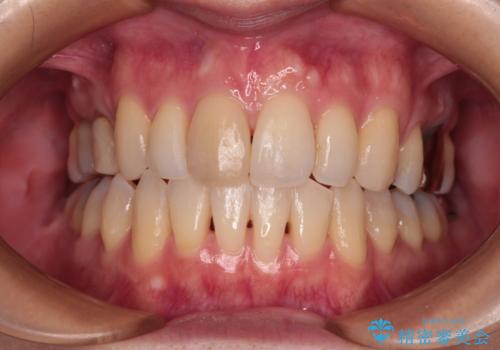

- クラウンがもげてしまった歯が抜歯と言われたとのことで来院された患者様です。

矯正治療中は汚れが溜まりやすく、歯肉からの出血が続きましたが、最終的には歯を保存して安定した状態で補綴治療を行うことができました。